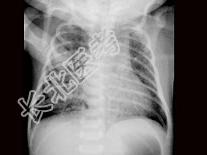

单项选择题患儿,男, 1天,生后呼吸困难, 羊水见胎粪污染,如图, 最可能的诊断为 ( )

E、胎粪吸入综合征